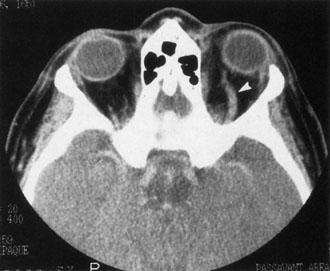

If NFM is suspected, MRI should be ordered of the orbits and brain to exclude noncontiguous intracranial anomalies.93 Magnetic resonance imaging demonstrates the dilated cystic spaces with either a hypointense (lymphatic cyst) or hyperintense (hemorrhagic cyst) signal on T1-weighted images, and a hyperintense signal on T2-weighted images (Fig. 10, A&B).94Layering may be seen within the cysts if there has been a recent hemorrhage leaving unresorbed blood. The CT scans of patients with a deep NFM show low-density, poorly defined masses behind the orbital septum in the extraconal and intraconal spaces, which may indent the globe.3 Calcification within the mass (Fig. 11) and inhomogeneous enhancement of the rim and focal areas within the lesion may be seen that corresponds to abnormal endothelially lined channels.3 Enlargement of the bony orbit can occur, particularly with combined lesions.3,89 If the diagnosis is still unclear, ultrasonography can be performed. A cystic orbital mass is seen on B-scan. A-scan shows features of a solid, cellular tumor: low reflectivity, regular homogeneous internal structure, and marked sound attenuation through the mass.3,89 Standard pulsed Doppler ultrasound confirms no intrinsic flow within the lesions.

Fig. 11. Axial computed tomography scan of patient in Figure 9, showing poorly defined orbital mass with calcifications. (Courtesy of Nancy A. Tucker MD, Illinois Oculoplastic Associates)